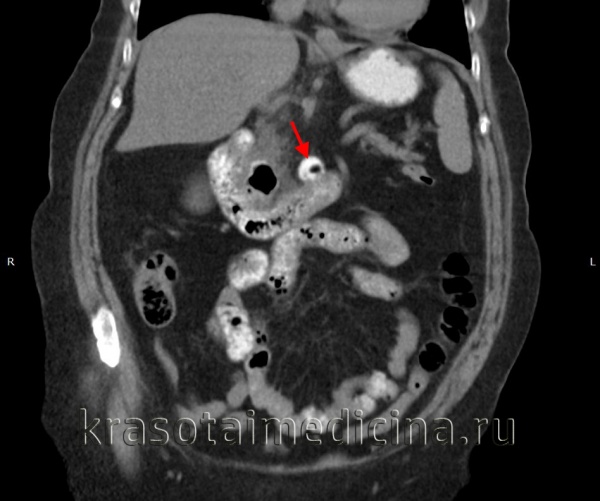

Дивертикул Меккеля у мужчины 23 лет.

(а, б) При контрастно-усиленной КТ в аксиальной (а) и коронарной (б) проекциях визуализировано прилегающее к петлям дистального отдела тонкой кишки трубчатое образование (изогнутая стрелка) с утолщенной стенкой,накапливающей контраст. Вокруг этого образования отмечено тяжистоеуплотнение жировой клетчатки (звездочка).

(в) Сцинтиграфия с использованием Тс-99м (пертехнетат): персистирующий фокус захвата препарата (изогнутая стрелка) в области правее и выше мочевого пузыря, что позволяет предположить наличие гетеротогшческой слизистой оболочки желудка.

(г) Макропрепарат: воспаленный дивертикул Меккеля (стрелки). Дивертикул Меккеля у женщины 51 года.

При КТ неосложненный дивертикул Меккеля трудно отличить от прилежащих нормальных петель тонкой кишки. Как и при УС, можно выявить образование со слепым концом, наполненное жидкостью или воздухом, анатомически связанное с петлей подвздошной кишки. Решающую роль в диагностике кровотечения из дивертикула Меккеля играет сцинтиграфия с применения технеция-99m (пертехнетат). Захват препарата в тонкой кишке может указывать на наличие гетеротопической слизистой оболочки желудка, которая служит причиной кровотечения. Непроходимость кишечника может быть вызвана ущемлением кишечной петли при образовании спаек вокруг дивертикула, перекрутом вокруг этих спаек, инвагинацией дивертикула или ущемлением дивертикула Меккеля в грыжевом мешке (грыжа Литтре). Чем крупнее дивертикул, тем больше вероятность развития непроходимости.

Идентификация слепого дивертикулярного мешка на уровне переходной зоны необходима при постановке корректного предоперационного диагноза при возникновении непроходимости. Информативные признаки, выявляемыми при КТ в случае дивертикулита Меккеля,— воспалительное утолщение стенки дивертикула с накоплением в ней контрастного вещества, наличие энтеролитов в просвете дивертикула, тяжистое уплотнение прилежащей жировой клетчатки и скопление жидкости.